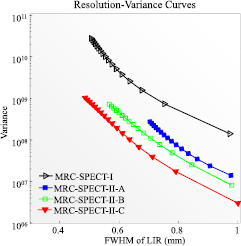

Standard image High-resolution image3.4. Quantitative studies

In figure 7, we quantitatively evaluate benefits of an ultra-high pixel resolution detector. For the target spatial resolution in the range between 0.7 mm and 1.0 mm, the image variance at the center of the FOV using the proposed HPWF detectors (MRC-SPECT-II-C, 100 μm detector pixels) was around five times less than that of the prototype HPWF detectors (MRC-SPECT-II-A, 400 μm pixels). Figure 7 also demonstrates that it was challenging for the prototype HPWF detector system (MRC-SPECT-II-A) to get resolution better than 0.7 mm.

Figure 7. Resolution-variance trade-off curves. The results were derived by selecting different-iteration images of the uniform phantom. Resolution and variance were evaluated at the center of FOV and obtained through simulation with 500 realizations.

Download figure:

Standard image High-resolution imageFigure 7 also assesses the performance benefit of the DOI effect. We show that for target spatial resolutions in the range between 0.5 mm and 1 mm, the image variance at the center of the FOV obtained with DOI resolution of 500 μm was less than half of that without DOI information.